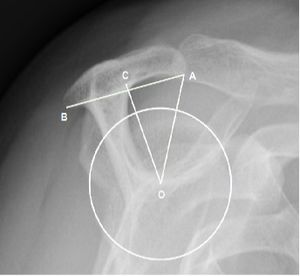

Acromial Index

Recently, Nyffeler et al. were interested in the implication of the extension of the acromion in the tears of the rotator cuff.[8] Their hypothesis was that a broad acromion implies higher deltoid ascending forces which favors impingement and degenerative changes. They therefore describe the radiological measurement of the acromial index which represents the ratio between the glenoid-acromion distance and that between the glenoid-greater tuberosity (Figure). There is therefore an association between a high acromial index and a degenerative lesion of the rotator cuff, thus allowing it to be predicted radiologically. Conversely, they describe an increase in compressive forces on the glenoid when the acromion is short and thus the acromial index low. This increase in compressive force would therefore favor the appearance of glenohumeral arthritis. These findings are confirmed by other studies that also demonstrate an association between elevated acromial index and a tear in the rotator cuff,[44][45] including one also demonstrating higher acromial index in patients with recurrences of postoperative rotator cuff tears.[46] The involvement of the acromial index in the pathologies of the rotator cuff is not however unanimous.[47][48][49] Hamid et al. do not demonstrate any significant association between elevated acromial index and rotator cuff disease,[49] while Kircher et al. do not show an association between a low acromial index and glenohumeral arthritis, which refutes the theoretical concept of a low acromial index resulting in increased contact pressure.[47] Furthermore, Melean et al. do not find correlation between acromial index and the rate of recurrence of rupture of the rotator cuff after surgery. The importance of the acromial index in assessing a shoulder radiograph remains controversial.